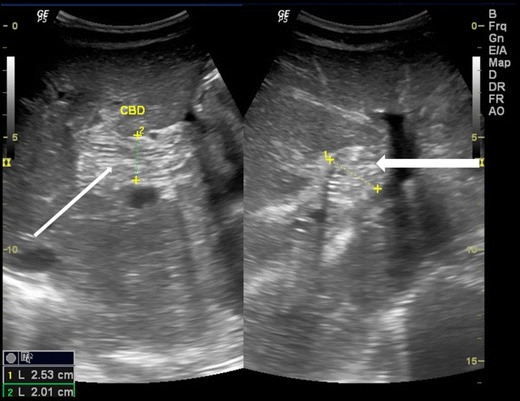

Intrahepatic ducts

Ascaris in the intrahepatic ducts are less common than the common bile duct. They may be seen in either lobes of liver with intrahepatic biliary dilatation. They are seen as similar tubular structures inside the hepatic ducts with a “strip sign” (Fig. 5a). On rare occasion, a “triple line” can also be appreciated on magnified view or with the use of high resolution linear array transducer (Fig. 5b). Calcified worms in the intrahepatic duct are also occasionally seen in asymptomatic patients on routine sonography (Fig. 6).

Fig. 5.

A 35-year-old female with acute pain in the right hypochondrium. (a) Ascaris seen in the left dilated intrahepatic duct (white arrow) and (b) magnified view of the ascaris in the dilated left intrahepatic duct, triple line seen (white thick arrow)

Fig. 6.

A 40-year-old female showing calcified shadow indicating calcified worms in the intrahepatic duct of the right lobe of liver (thick white arrow)